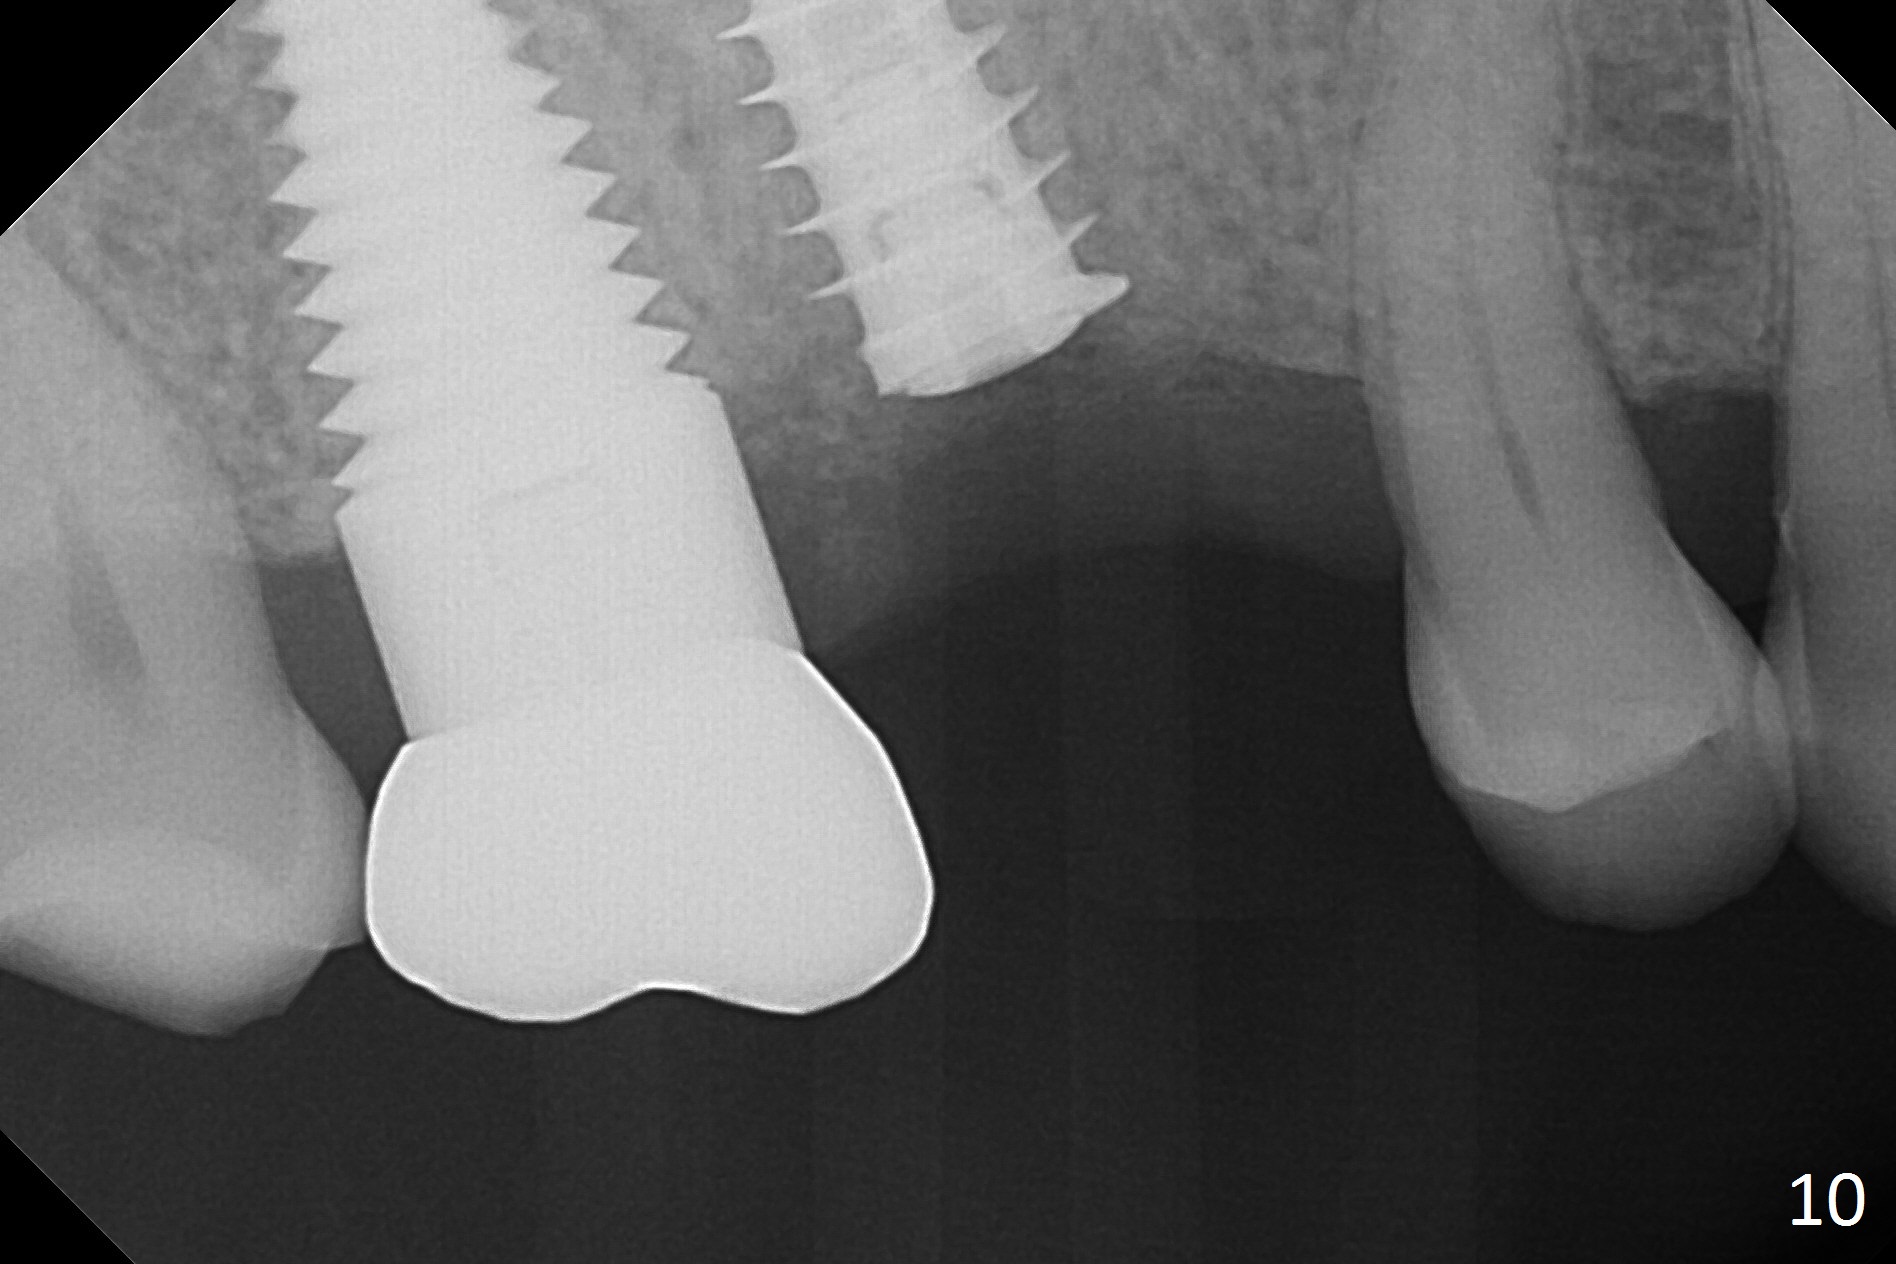

In fact, local anesthesia is required to remove the healing abutment. The gingival cuff is apparently healthy. The implant does not turn when torque reaches 45 Ncm. After placing a healing screw, PAs seem to show that the implant is osteointegrating (Fig.10,11).